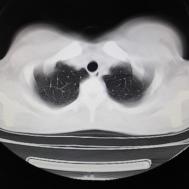

支原体肺炎1例CT影像表现

性别:女,年龄:26岁,低热,轻微胸痛,支原体阳性

[影像描述]

两肺内及胸膜下多发斑片状高密度影,部分病灶密度较淡,部分实变,边缘可见渗出改变。